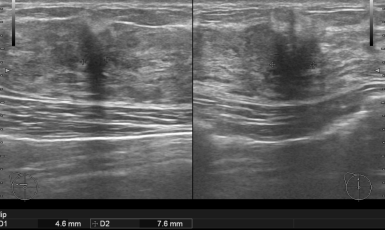

302번째 갑상선암 진단사례 (2019년5월20일) 몇주전부터 목이 불편하고 삼킬때마다 통증이 있어 갑상선 관련 질환인지 확인하기 위해 저희 병원에 내원해 주신 환자분이셨습니..